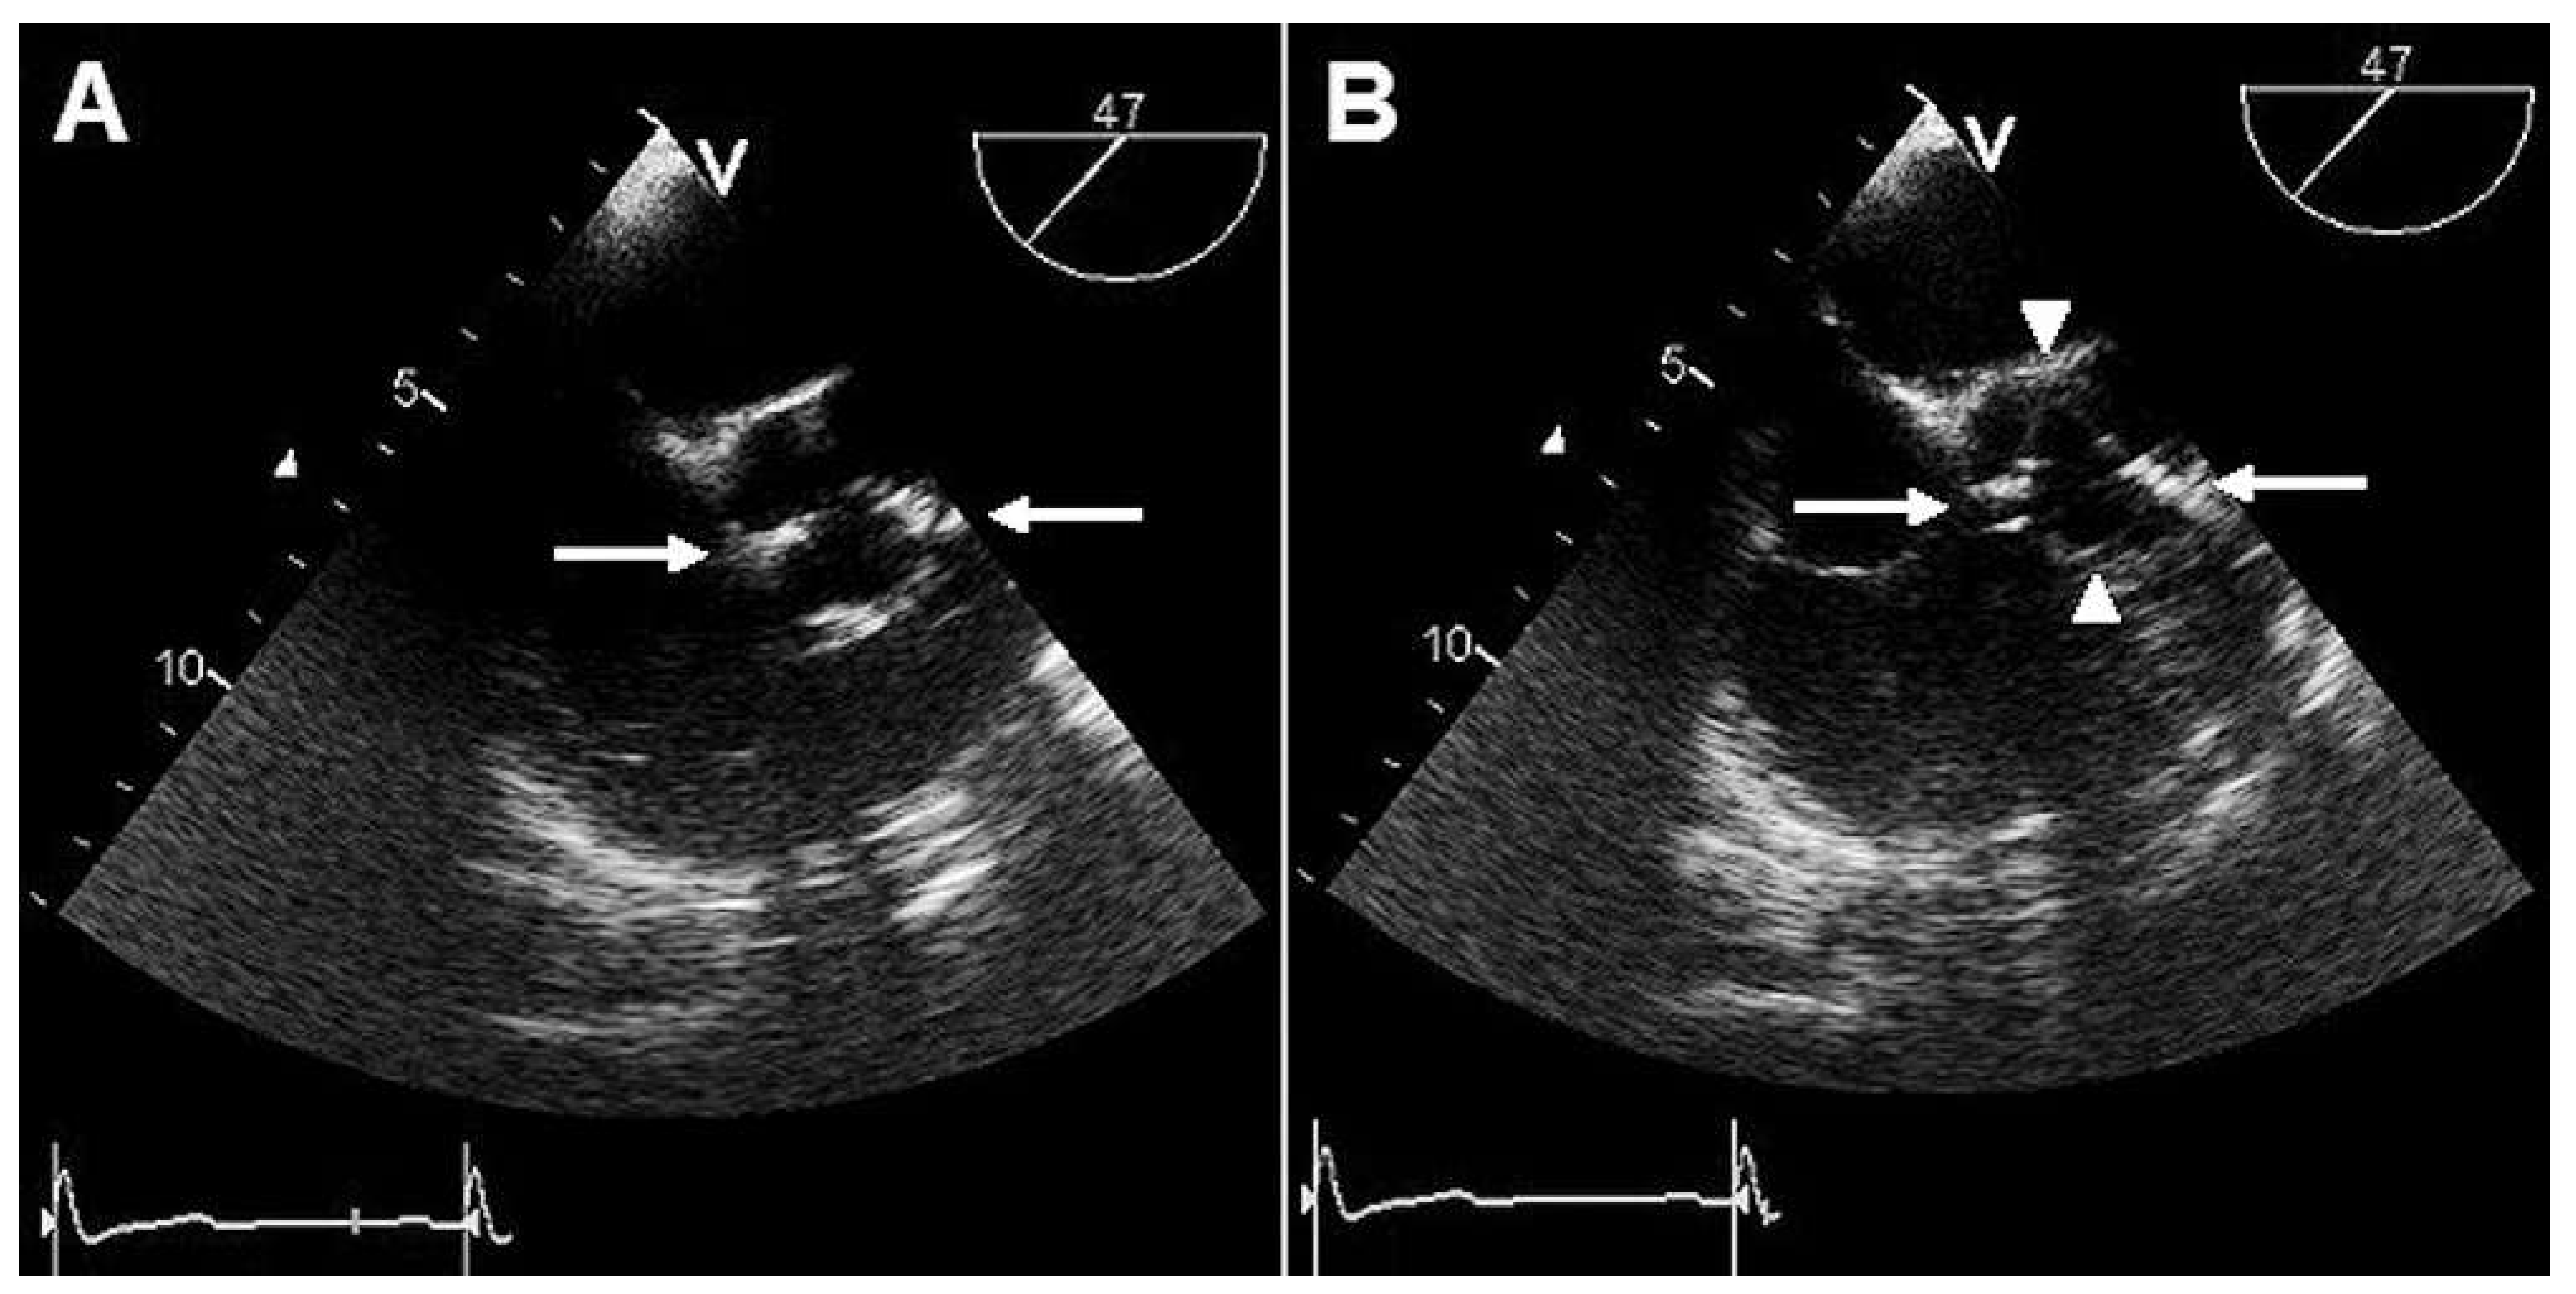

Case report